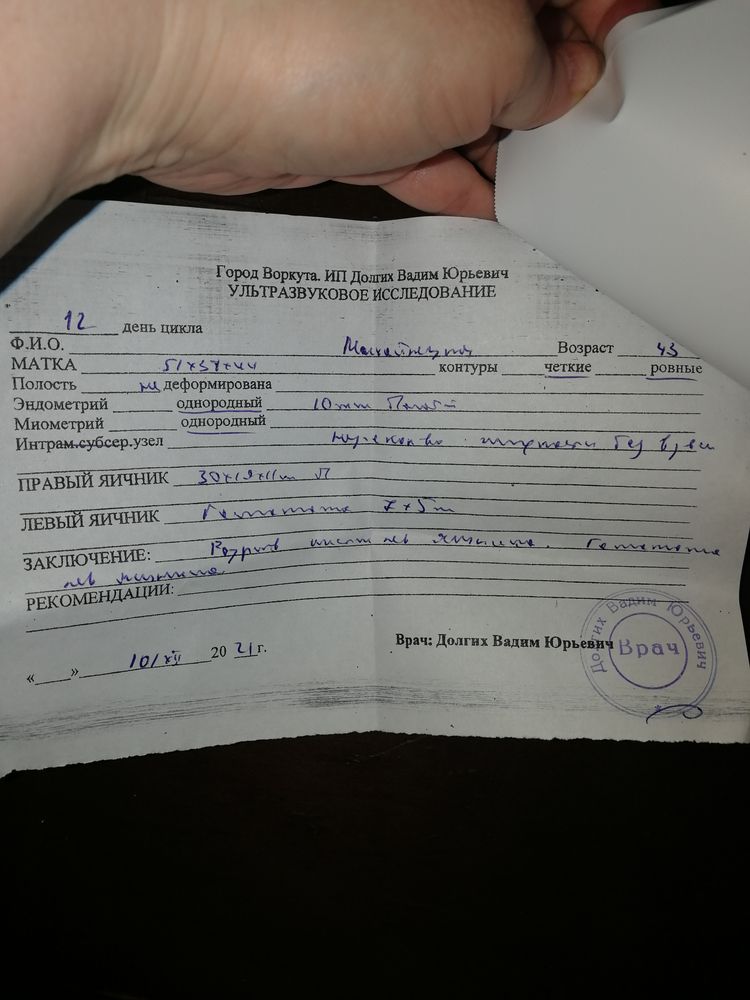

Как и думала - гематома ЛЯ 7х5 мм. О в процессе. Сколько вышло ЯК не узнать, очень много жидкости в ПМП, явно не от одного ДФ. Крови нет, хорошо Дицинон пила, свечи ставила Индометацин. Эндик 10 мм. В общем, отправили к мужу делать ляль.